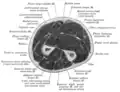

Click image to enlarge - ulnar nerve is visible in lower left